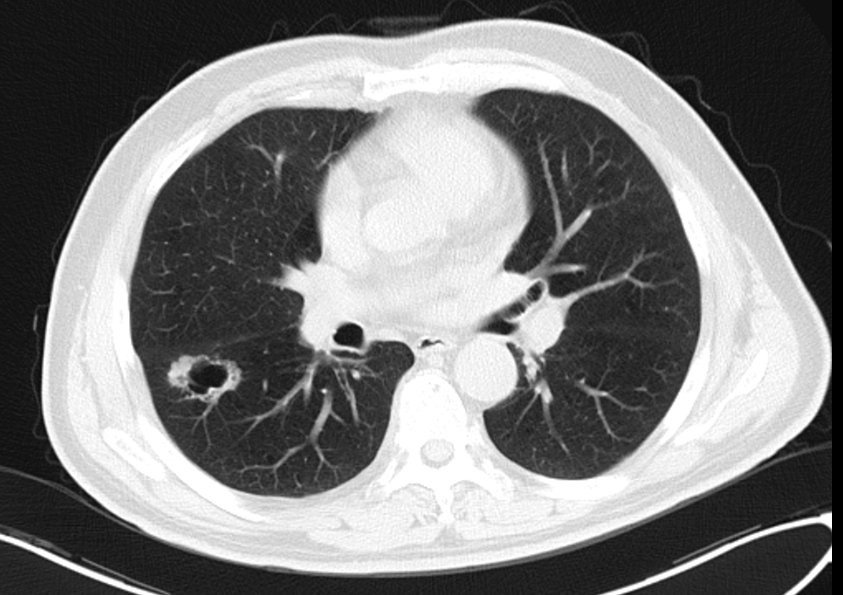

某男性,67岁,患者患者2015年11月起无明显诱因下出现间断轻咳,咳少量白痰,有时咳少量白色泡沫粘痰或黄色粘痰,无咯血,无胸闷胸痛,无气促不适,一直未在意。2016-05-08体检时发现肺部异常,在江苏省某医院肺CT检查,提示“右肺空洞”,后转入我院。

(2015年5月8日胸部CT提示右肺下叶背段空洞)